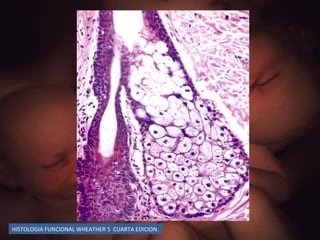

GLANDULAS  SEBACEAS HISTOLOGIA FUNCIONAL WHEATHER`S CUARTA EDICION. EMBRIOLOGÍA CLÍNICA. KEITH MOORE. 6TA EDICIÓN newbornvernix.jpg

HISTOLOGIA FUNCIONAL WHEATHER`S  CUARTA EDICION.